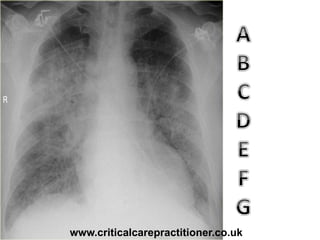

TECHNICALS

AIRWAY

BONES

cARDIAC

DIAPHRAGM

GASTRIC BUBBLE

EQUAL LUNG FIELDS